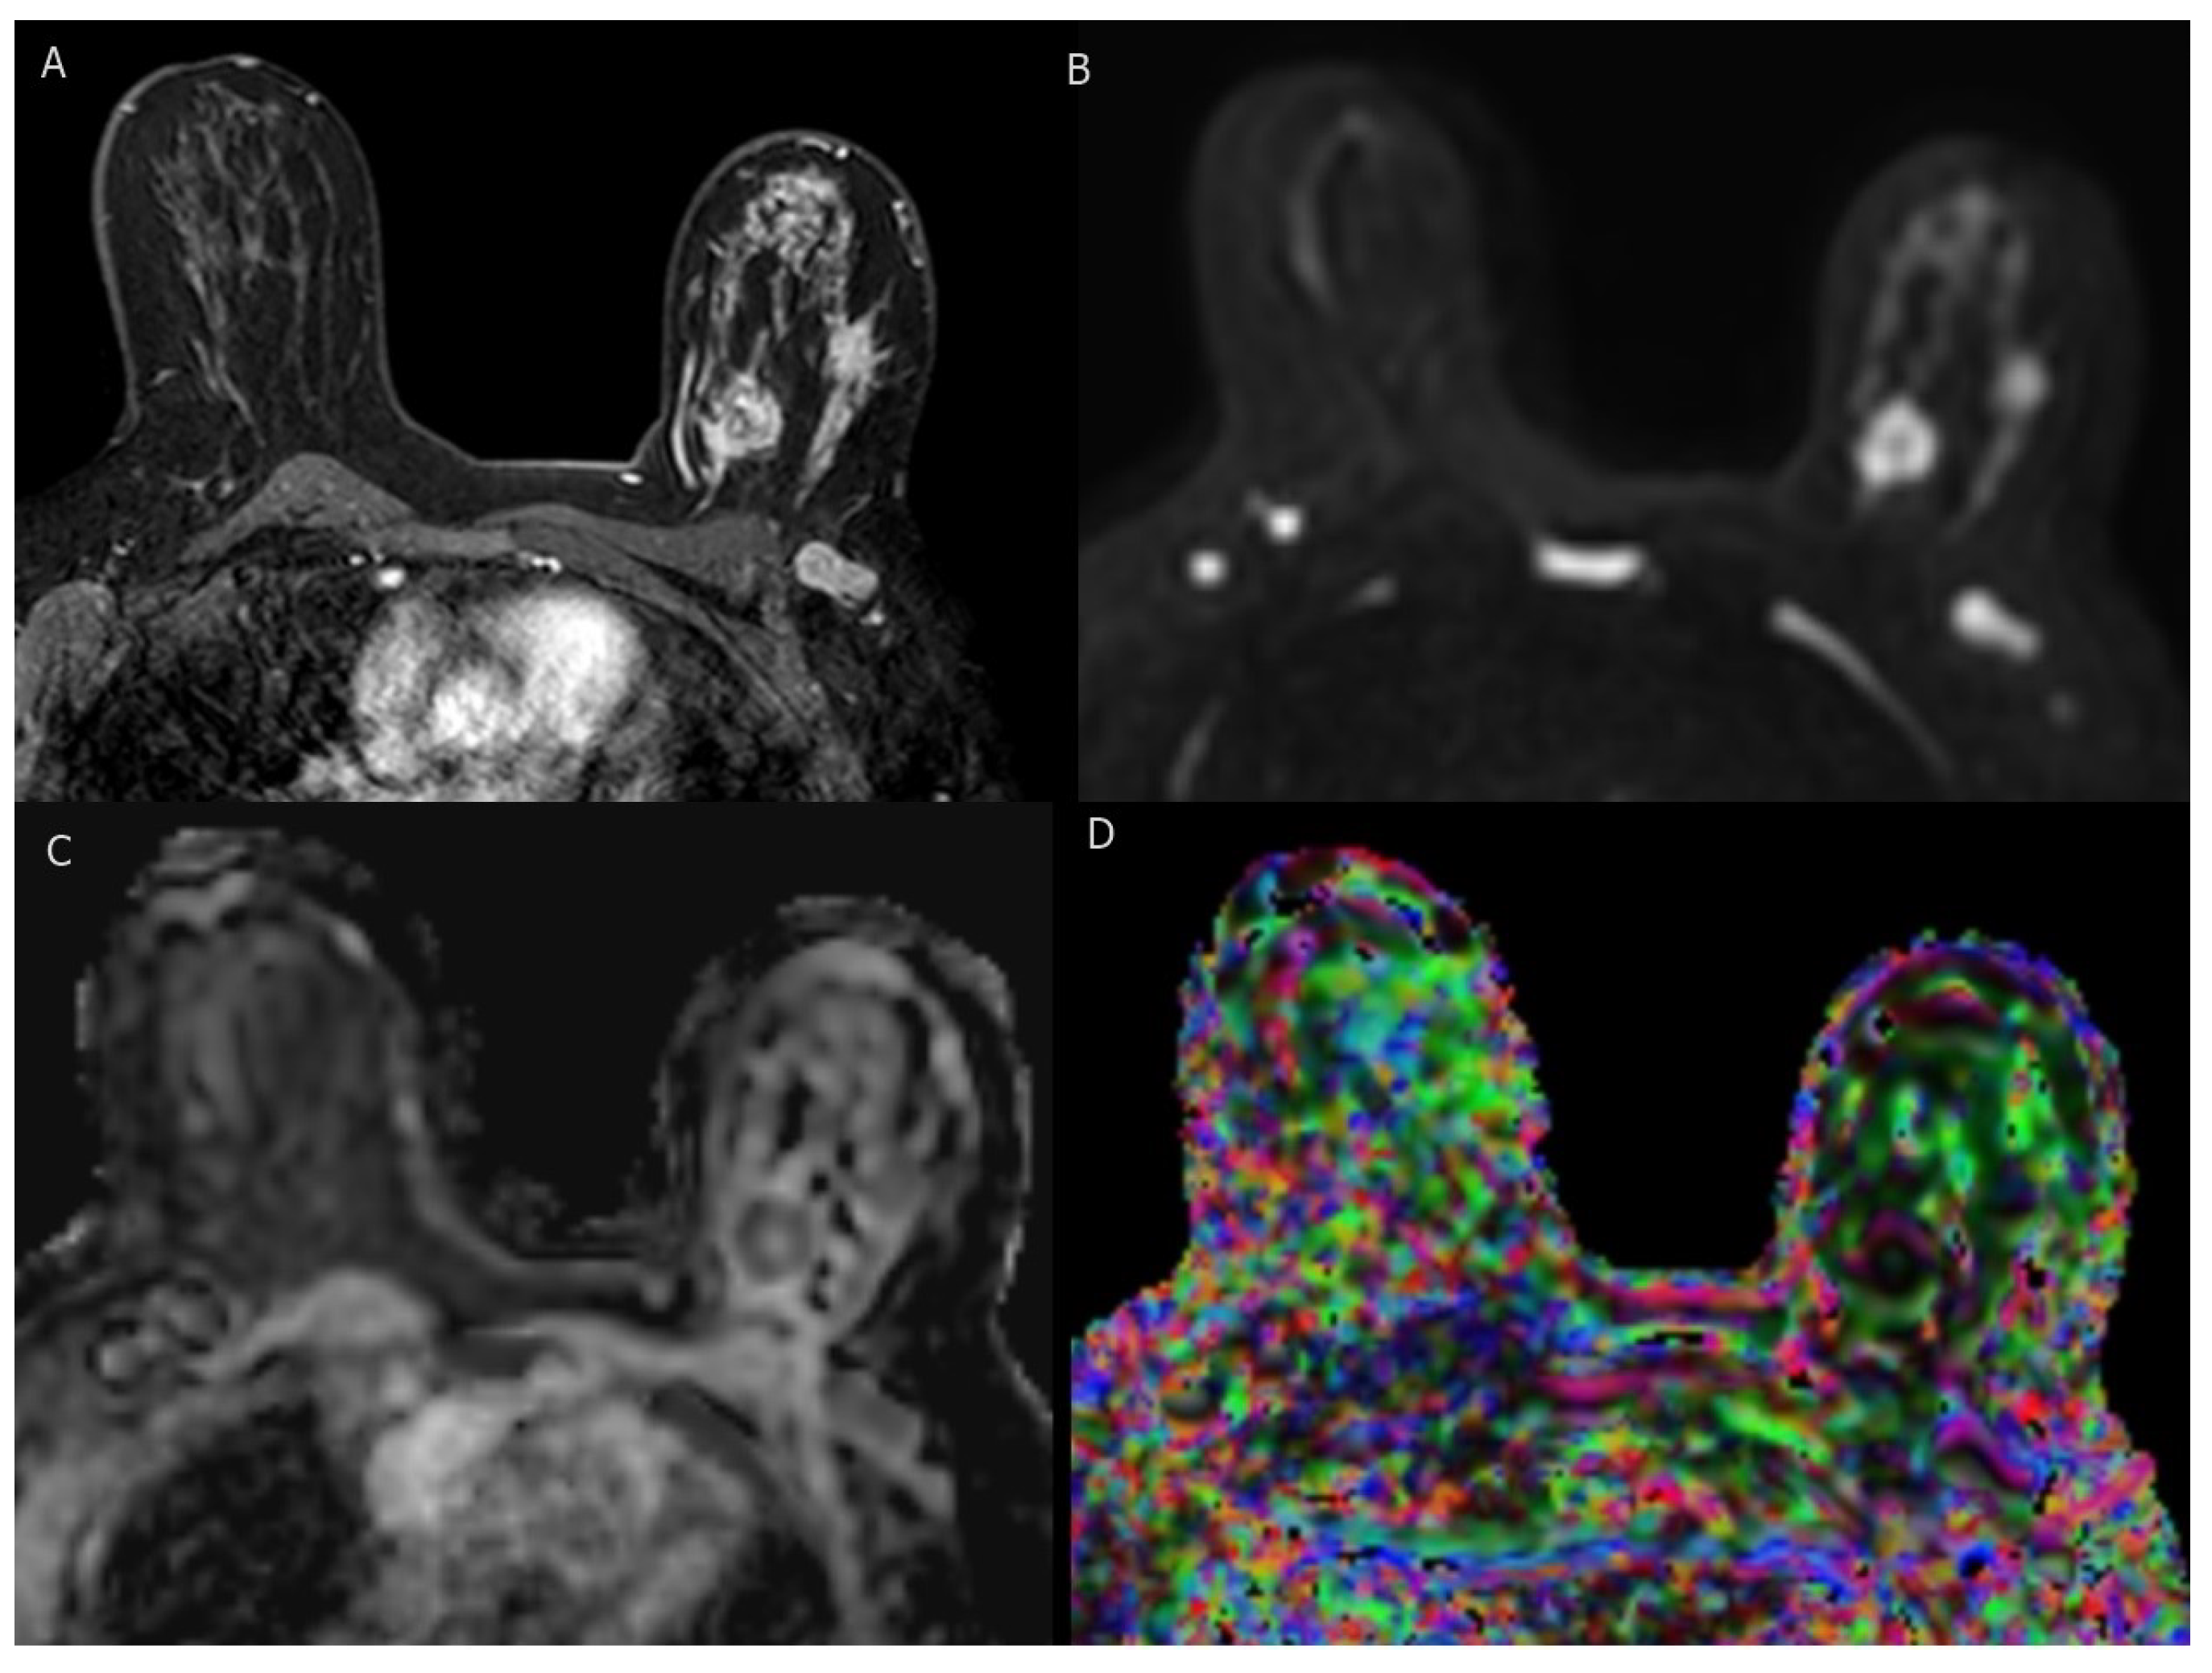

Figure 3.

BI-RADS category 5: 37-year-old woman with triple-negative invasive ductal carcinoma. (A) axial T1-weighted fat-saturated dynamic contrast-enhanced MR image shows two irregular masses of heterogenous enhancement with ipsilateral suspicious axillary LN. (B–D) axial DWI (b = 1000), corresponding ADC map, and DTI image (colored FA map ) show marked diffusion restriction of two masses and axillary LN with low ADC values ( mm /s, mm /s and mm /s ) and high FA values (0.57, 0.56 and 0.54), respectively.